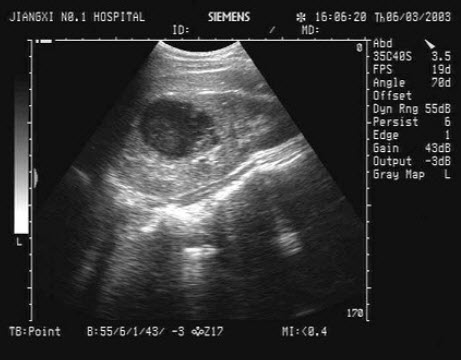

56、单项选择题

患者,急性胰腺炎治疗后,超声见胰管内多个强回声光团,后伴声影,如图所示,考虑为()

A.胰腺胰管结石

B.胰腺脓肿

C.胰腺肿瘤

D.胰腺假性囊肿

E.胰腺胰管钙化